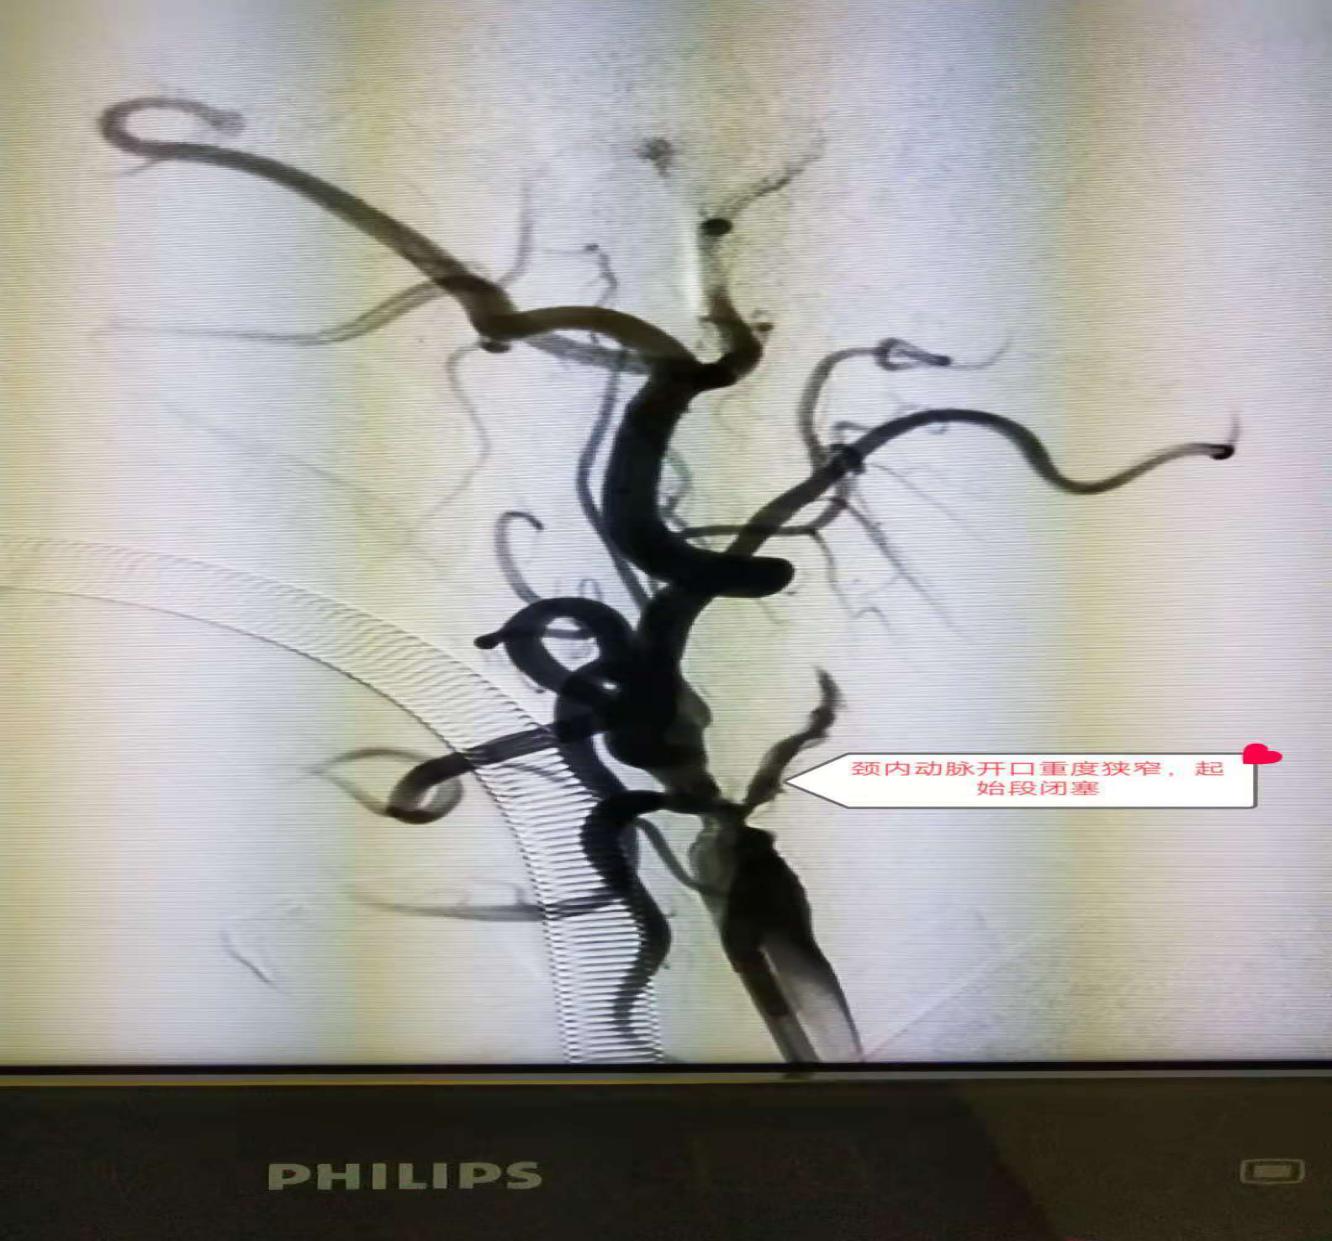

介入血管外科张煜杰主任团队先为患者实施血管造影,明确梗死血管和脑组织范围,造影剂显影显示,该患者右侧颈内动脉开口重度狭窄,颅内段血流缓慢,大脑中动脉堵塞,是一复杂的串联性血管病变。知晓患者病情后,立即为患者实施“颈内动脉支架成型加大脑中动脉取栓术”,先将导丝伸入颈动脉血管,用支架将狭窄处血管撑起来,然后将患者颅内血管的血栓一点点的取出来。